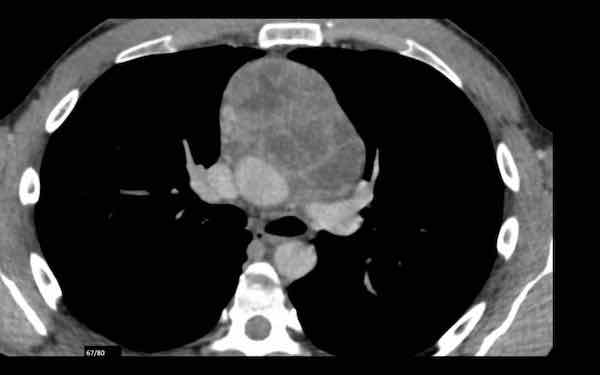

Các hình ảnh này của một phụ nữ 65 tuổi có tiền sử mắc bệnh Graves, một rối loạn tự miễn liên quan đến tình trạng cường chức năng tuyến giáp.

CT được thực hiện vì lý do ho ra máu.

Hình ảnh

Có một tuyến ức to lớn, cồng kềnh chứa mô mỡ đại thể.

Đây là hình ảnh điển hình của tăng sản tuyến ức.

Tăng sản tuyến ức trong bệnh Graves có liên quan đến tình trạng dư thừa hormone tuyến giáp và kháng thể kháng thụ thể thyrotropin.

Tình trạng này thường cải thiện sau khi điều trị thành công bệnh Graves.